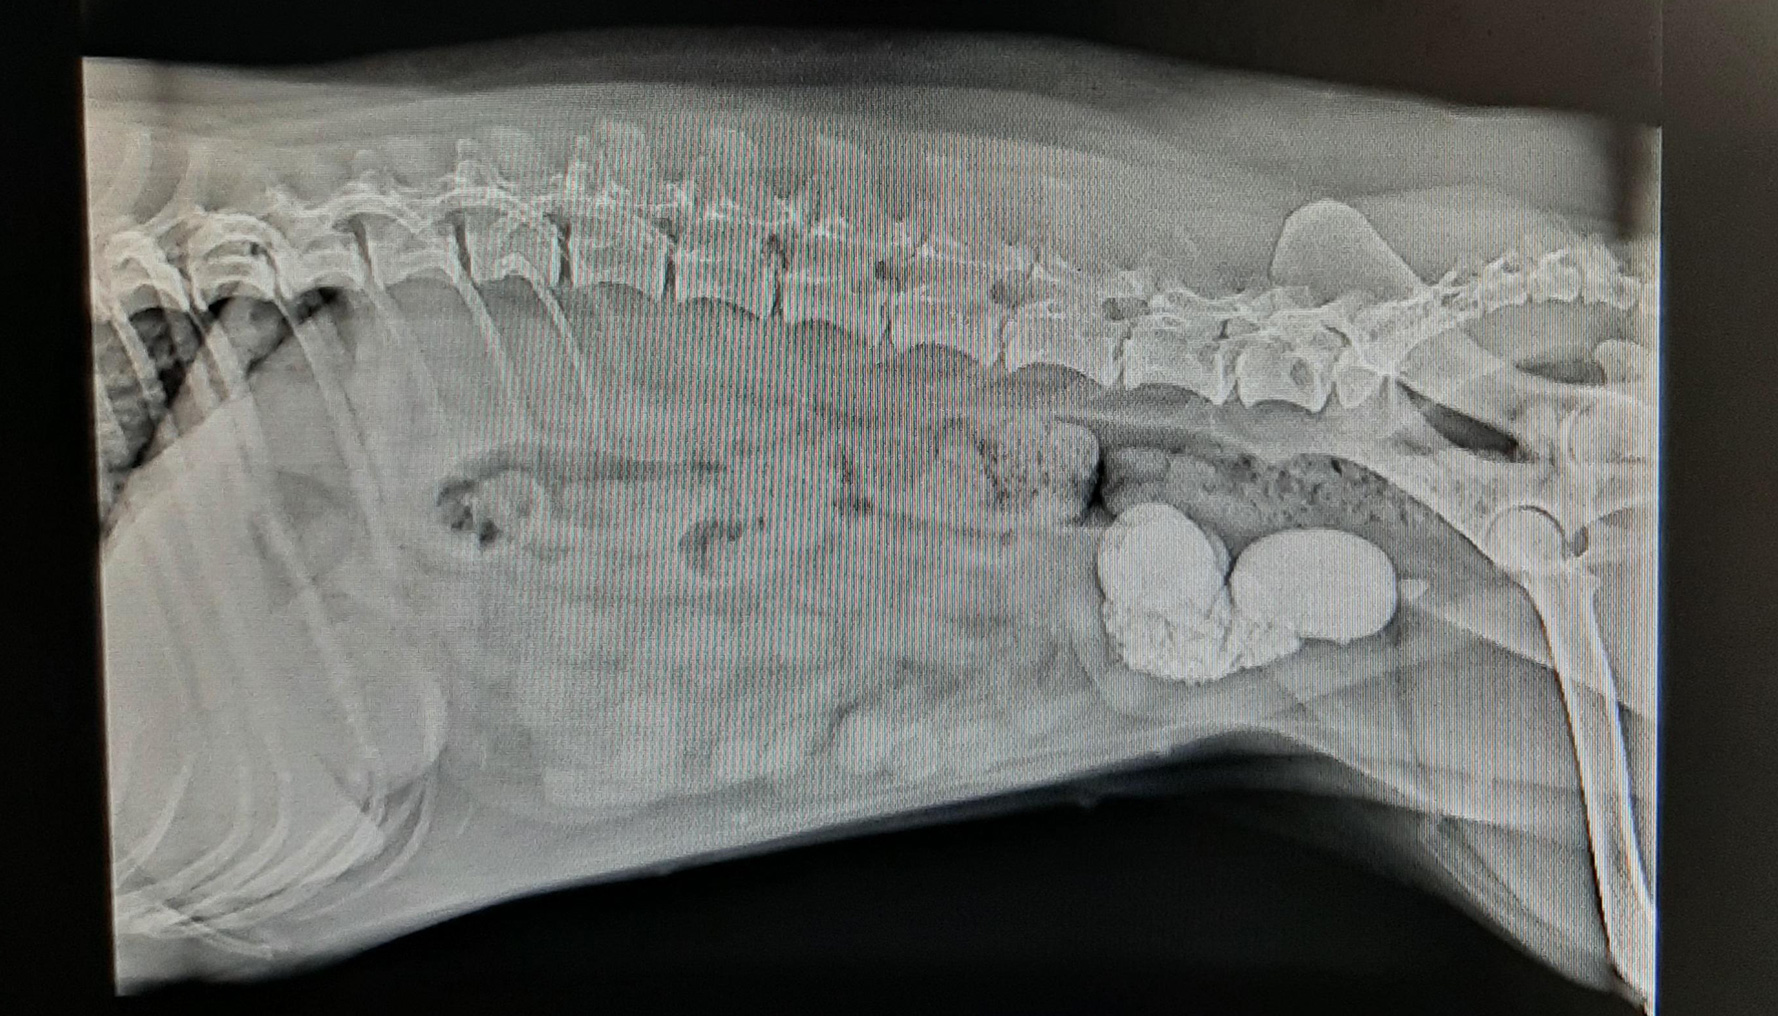

Cystotomy is a surgical procedure in which an incision is made into the dog's urinary bladder. The procedure can be done for many reasons, the most common being to facilitate removal of bladder and urethral stones.